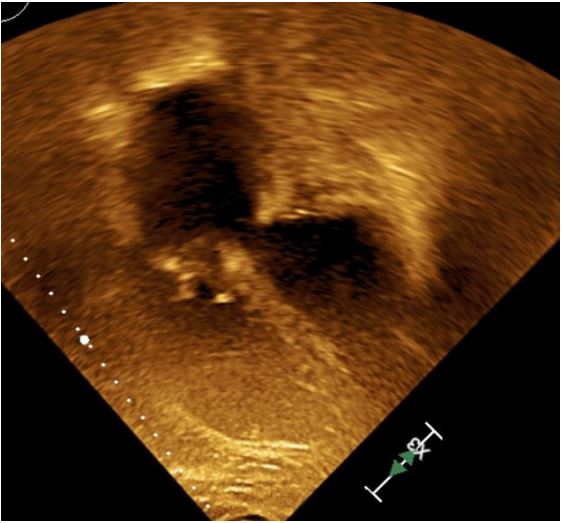

Echocardiogram (Figures 1,2) and MRI (Figure 3) showed severe dilation of the right atrium, severe tricuspid regurgitation, decreased ventricular systolic dysfunction, and dilated right ventricle. Based on his echocardiogram & MRI, it was determined that he would benefit from a tricuspid valve replacement. Preoperative type and cross was positive for cold agglutinin and needed appropriately matched blood.

Figure 3: Pre Op MRI showing Axial cine sequence 4 chamber view, showing dilated Right Atrium (RA) & dilated Right Ventricle (RV).